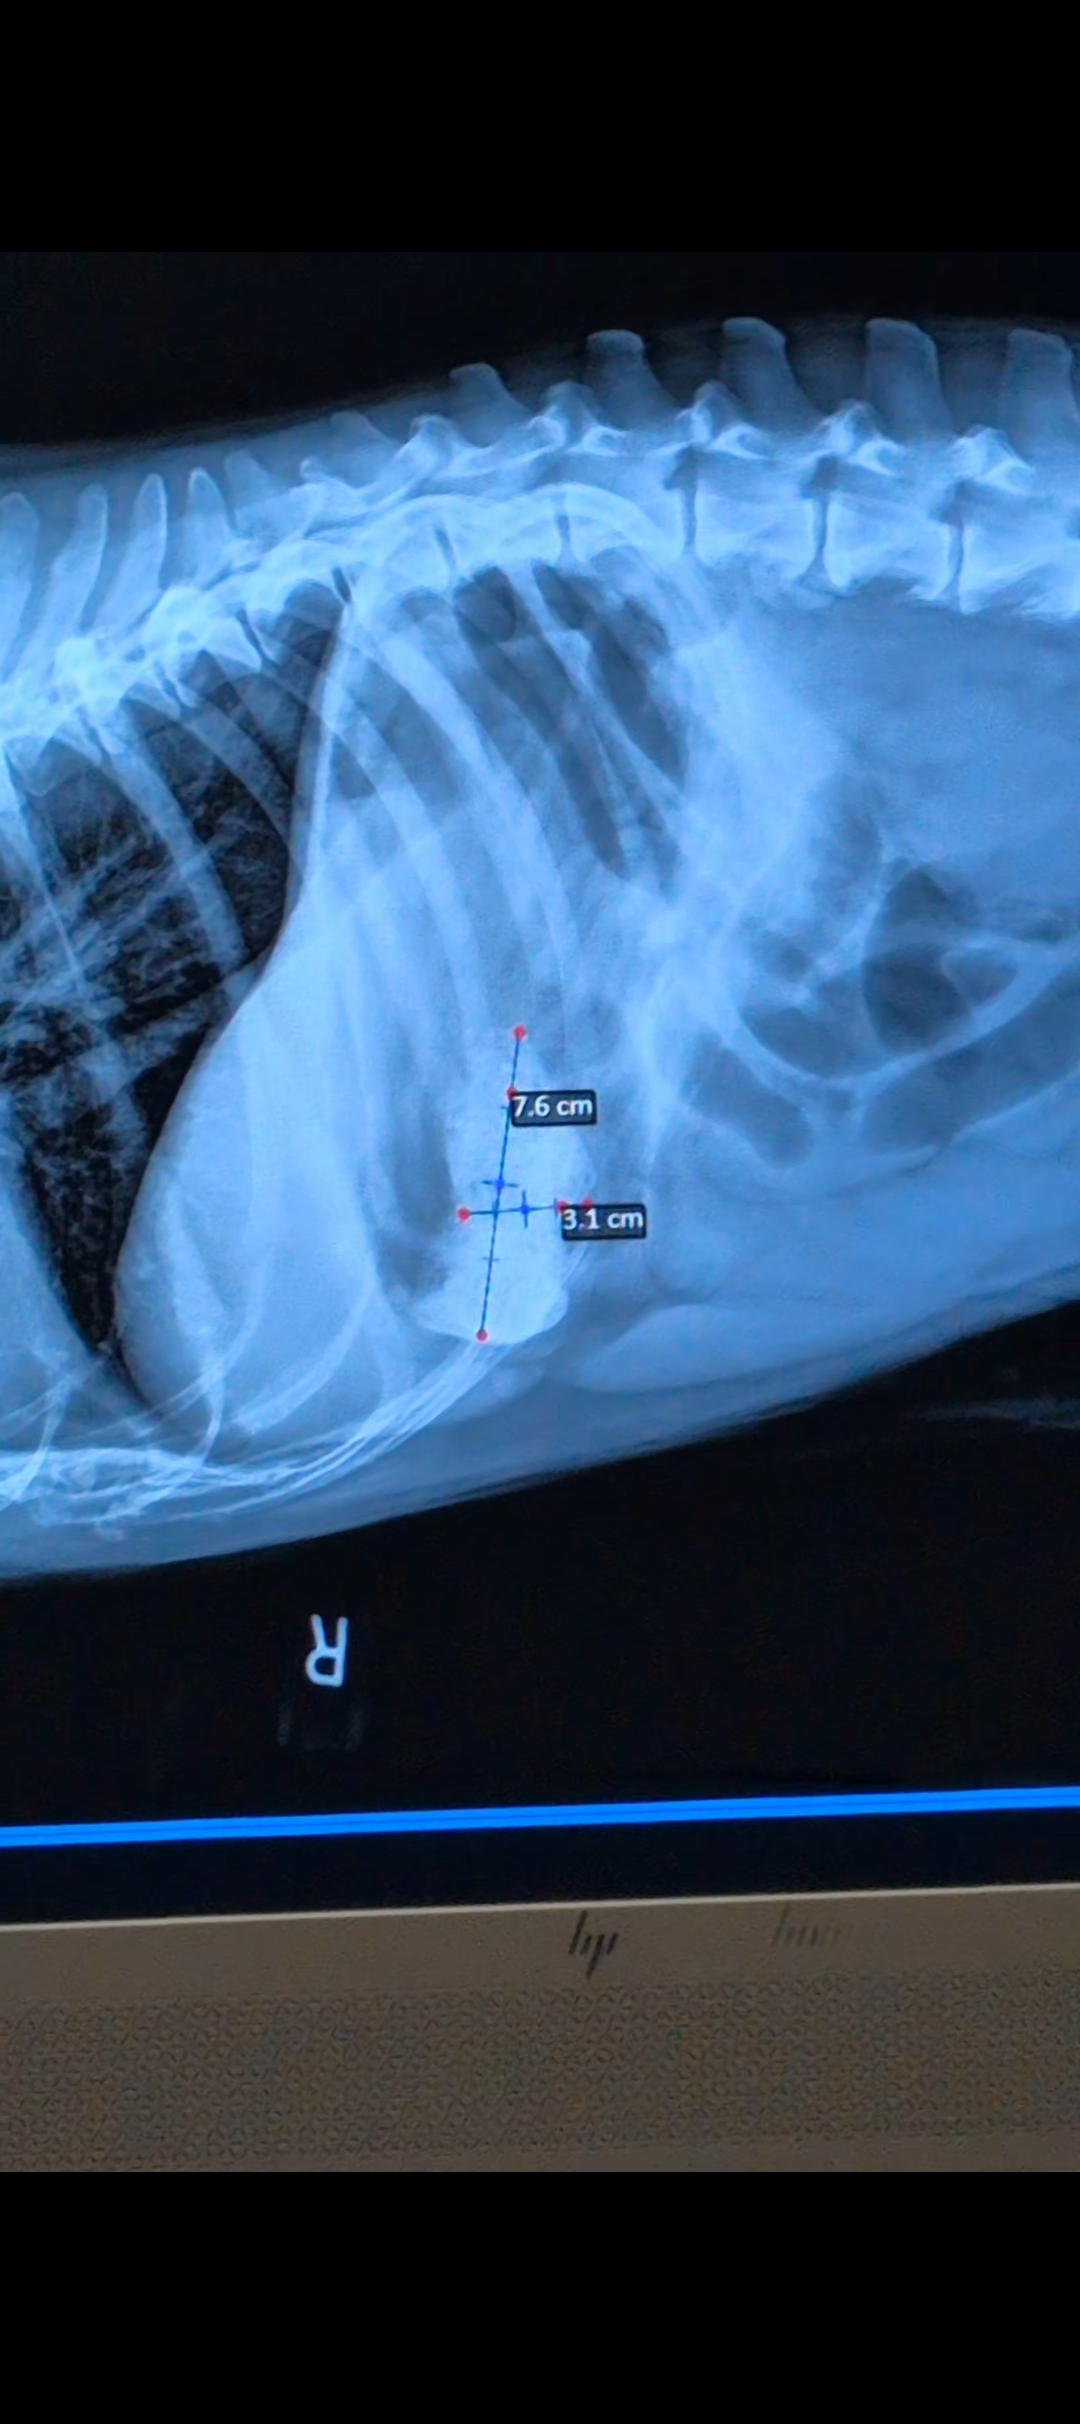

Hello, my name is Destiny and my fiance's name is Natasha she goes by Tasha we are in need of help raising funds to get surgical treatment for our very beloved CAPONE he's our 12 year old senior American Bulldog he's my fiance's BEST FRIEND LITERALLY. Her main man! Everyone who's met Capone falls in love he's just the sweetest boy you could ever meet! A while ago he started acting extremely lethargic, not eating, not sitting down and not very alert at all.. We took him to the vet and they have charged us $1,500 for X-rays and blood work to find that he has a blockage in his stomach and we desperately need help to save him and get him into surgery! Please, if you find it in your heart to help in any way we would greatly appreciate it. My birthday is also tomorrow 05/31 this would be the best birthday gift!! <3 I couldn't imagine not saving him.